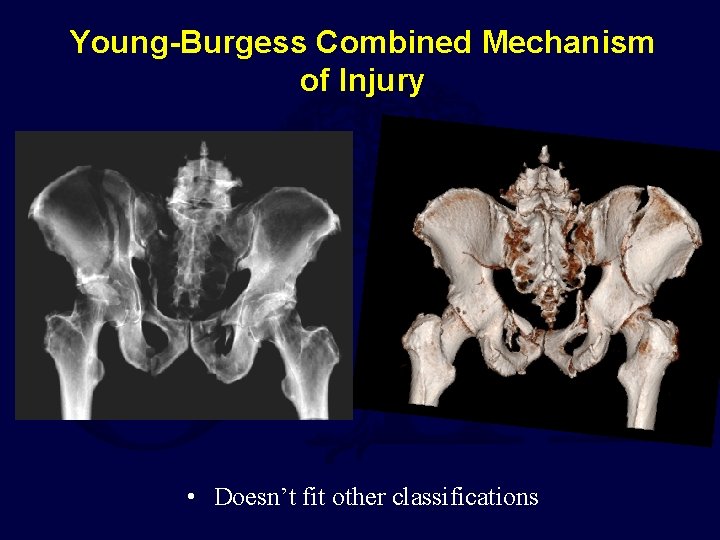

Young-Burgess Combined Mechanism of Injury • Doesn’t fit other classifications